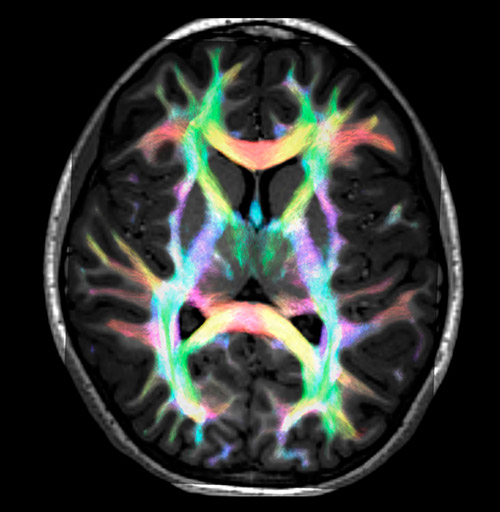

Super-resolution directionally encoded color track-density imaging overlaid on T1-weighted structural MRI.

All images were created from the same acquisition in a child using Ingenia 3.0T CX and 32-channel dS Head coil. Diffusion data was acquired at b-values 0, 500, 1000, 2000, 3000. The use of high b-values (3000 s/mm2) effectively suppresses extra-axonal water signal and provides high angular resolution.

Fiber tracking from the left and right hippocampi to the fornix (green), and the corticospinal track based on a seed region of the posterior limb of the internal capsule.

Fiber tractography of the corticospinal tract with seed region of the posterior limb of the internal capsule. Different processing based on the same data.

Data processing was performed using open source software. Fiber tracking was performed using the MRtrix package (J-D Tournier, Brain Research Institute, Melbourne, Australia, https://github.com/MRtrix3/mrtrix3), Tournier et al. 2012. DEC TDI based on F Calamante et al 2010.